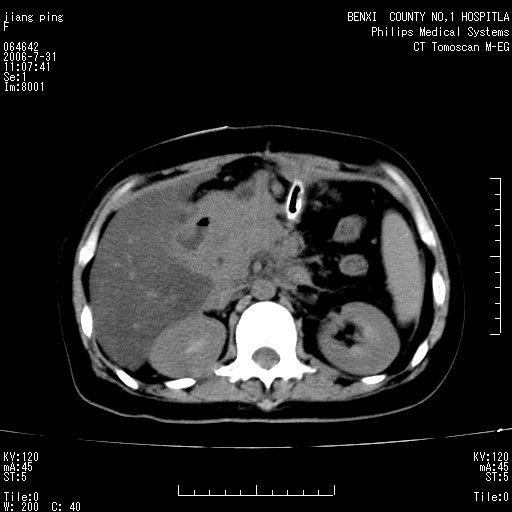

以下是引用晓杰在2006-8-1 9:01:00的发言:[br]支持营养不良导致脂肪肝。[br]胰头增大界限不清,考虑为胰腺炎破坏十二指肠粘膜、肠壁增厚、肠腔狭窄,并与胰头粘连所致

以下是引用jiajie在2006-7-31 20:34:00的发言:[br]支持营养不良导致脂肪肝。[br]胰头增大界限不清,考虑为胰腺炎破坏十二指肠粘膜、肠壁增厚、肠腔狭窄,并与胰头粘连所致。